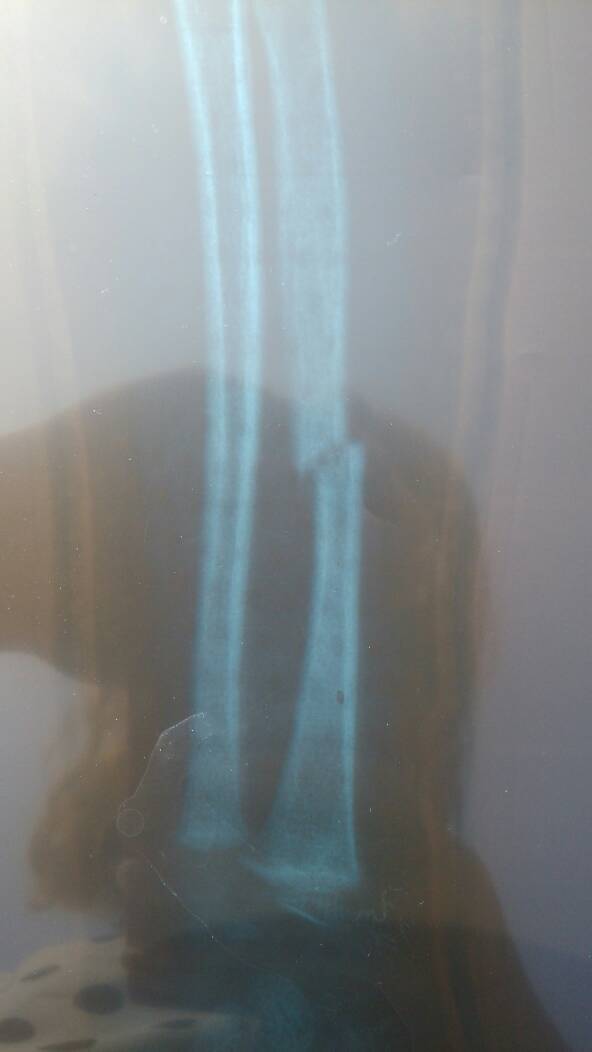

小孩骨折需要动手术吗?需要打消针或者贴膏药吗?去医院做了复位,可是没复动,也没打石膏,就弄了一个胶壳子说是支架,,今天都6天了,手臂还是肿的,要多久才能消肿

这种情况一般三甲医院都建议消炎后打内固定,如果现在延误了,到时候还是要敲断新长的骨痂再做手术。